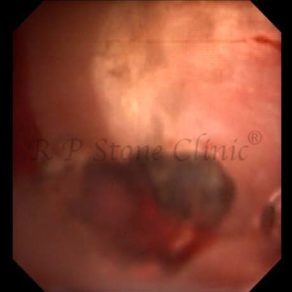

Kidney stone is a solid mass of CRYSTALS. It is the process of crystallization which initiates the formation of kidney stones. This happens in nephrons or units of kidney. Once a small crystal is formed, it can both grow & unite with other crystals leading to the formation of small concretion which eventually forms a stone. Once these large crystals detach from the collecting ducts, the process of stone formation starts in the renal collecting system. A recurrent kidney stone former is advised to know a little bit about something known as Randall’s plaque. Alexander Randall discovered plaques on the renal papillae eight decades back based on examination of 1154 pairs of autopsied Kidneys. He described these renal papillary lesions as cream colored or milk patch areas composed of calcium phosphate & calcium carbonate. These plaques could act as NIDUS for formation of KIDNEY STONE. Calcium Oxalate stone can form on this nidus & then detaches from this plaque to become a free floating stone in the collecting system of kidney

These images are taken as snap shots from the video recording of RIRS Surgery done at our hospital. These are Randall’s Plaques seen with Digital FLEX XC & Digital FLEX XC S. The cream or whitish patches are seen on the tips of RENAL PAPILLAE as seen in images below.